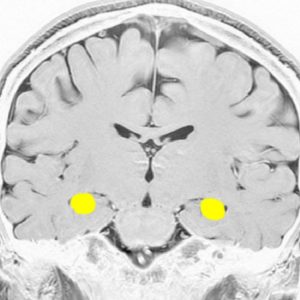

海馬

両側の側頭葉の内側にあり,学習,記憶,空間認識(spartial awareness。物体のある場所・大きさ・形・速さ・向き・物体同士の位置関係などを素早く正確に認知する能力)を司ります

記憶に関しては左側の海馬に優位性が大きいです

記憶の中枢であり,この部位の機能低下は認知症を招きます

アルツハイマー病の原因ともなる部位です